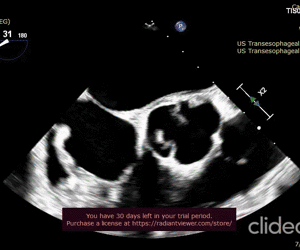

Cryptic Septic Endocarditis and Systemic Thromboembolism Triggered by Oral Microflora - USA

https://doi.org/10.59667/sjoranm.v23i1.16

This unique clinical case underscores the pathogenic nature of oral commensal microbial flora such as Streptococcus Anginosis in provoking infective endocarditis of physiologically normal native heart valves despite the absence of priming systemic risk factors. Understanding the triggering events for this pathological transformation of Stroptococcus Anginosus in normal patients is very much necessary. This will allow the clinicians to anticipate this transpiration in the clinical settings and execute appropriate therapeutic measures to minimize the morbidity and mortality.